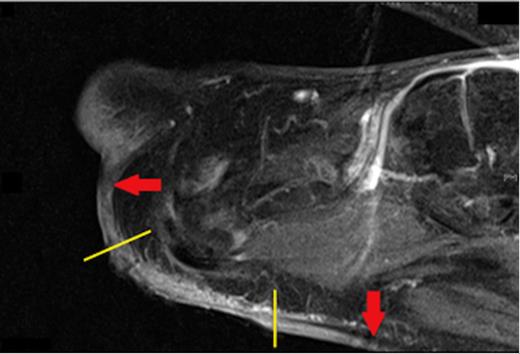

There was no loco-regional lymphadenopathy. However, palpation of the surrounding skin revealed a significant area of induration beyond the edges of the ulcer (Fig. 1). A magnetic resonance image (MRI) of the foot demonstrated an ill-defined mass spreading along the subcutaneous fat from the superficial margin of the plantar plate of the first metatarsal-phalangeal joint to the proximal margin of the forefoot (Fig. 2). In context of the clinical presentation, the patient was diagnosed with infiltrative SCC and a left forefoot amputation was performed.

Sagittal view of a T1 weighted MRI showing the extent of subcutaneous spread of the Squamous Cell Carcinoma (red arrows) beyond the visible edges of the ulcer (yellow lines)